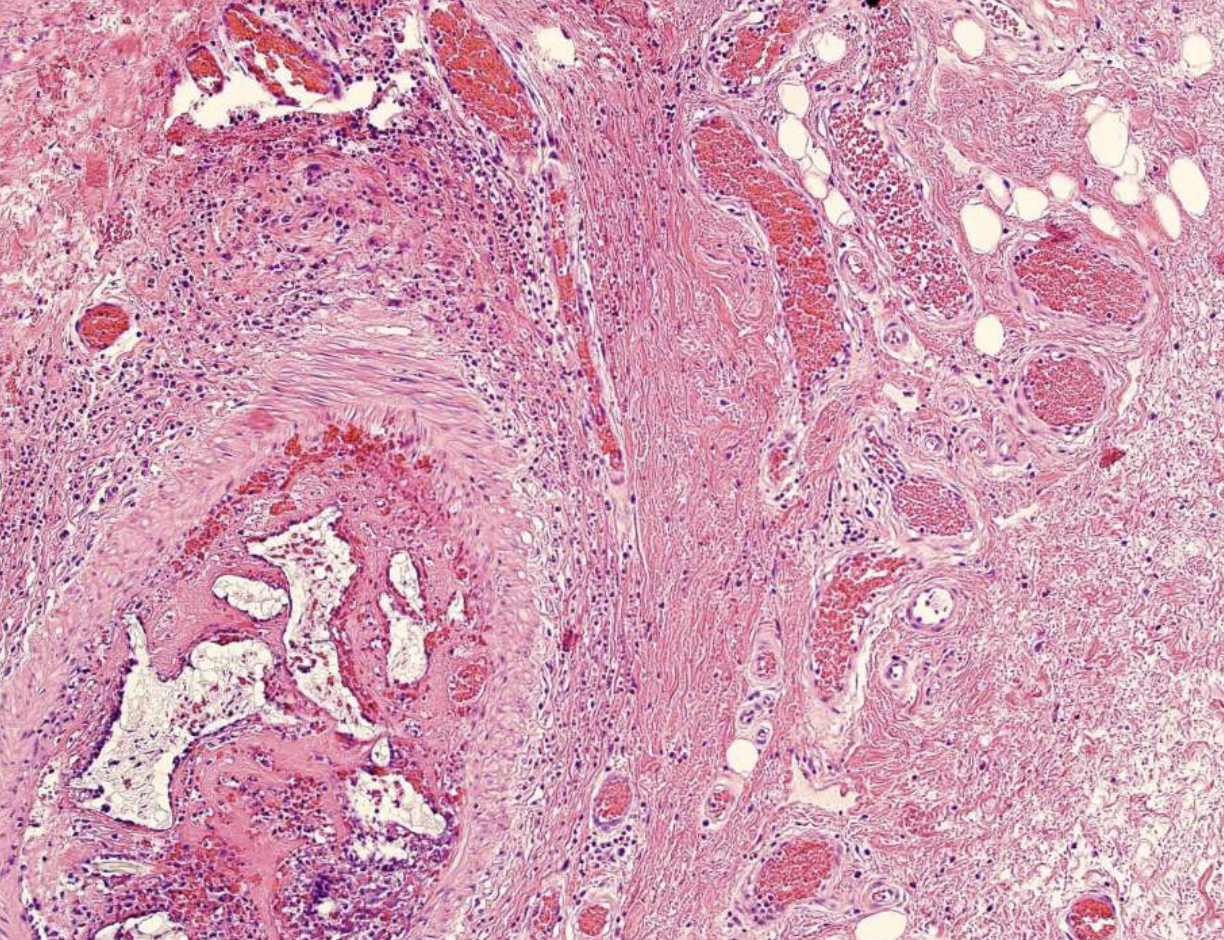

follicular pattern hisopath features of ameloblastomas

nests of epithelium

island centers resembling stellate reticulum

peripheral columnar cells with nuclei polarized opposite basement membrane (sub-nuclear vacuolization)

mature fibrous background